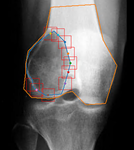

Knee Patella Malalignment

Knee Patella Malalignment AI

Automatic Diagnosis on X-ray. Measurement of Install-Salvati, Caton-Deschamps.

Aryan Kaul, Jason Pai, et al.